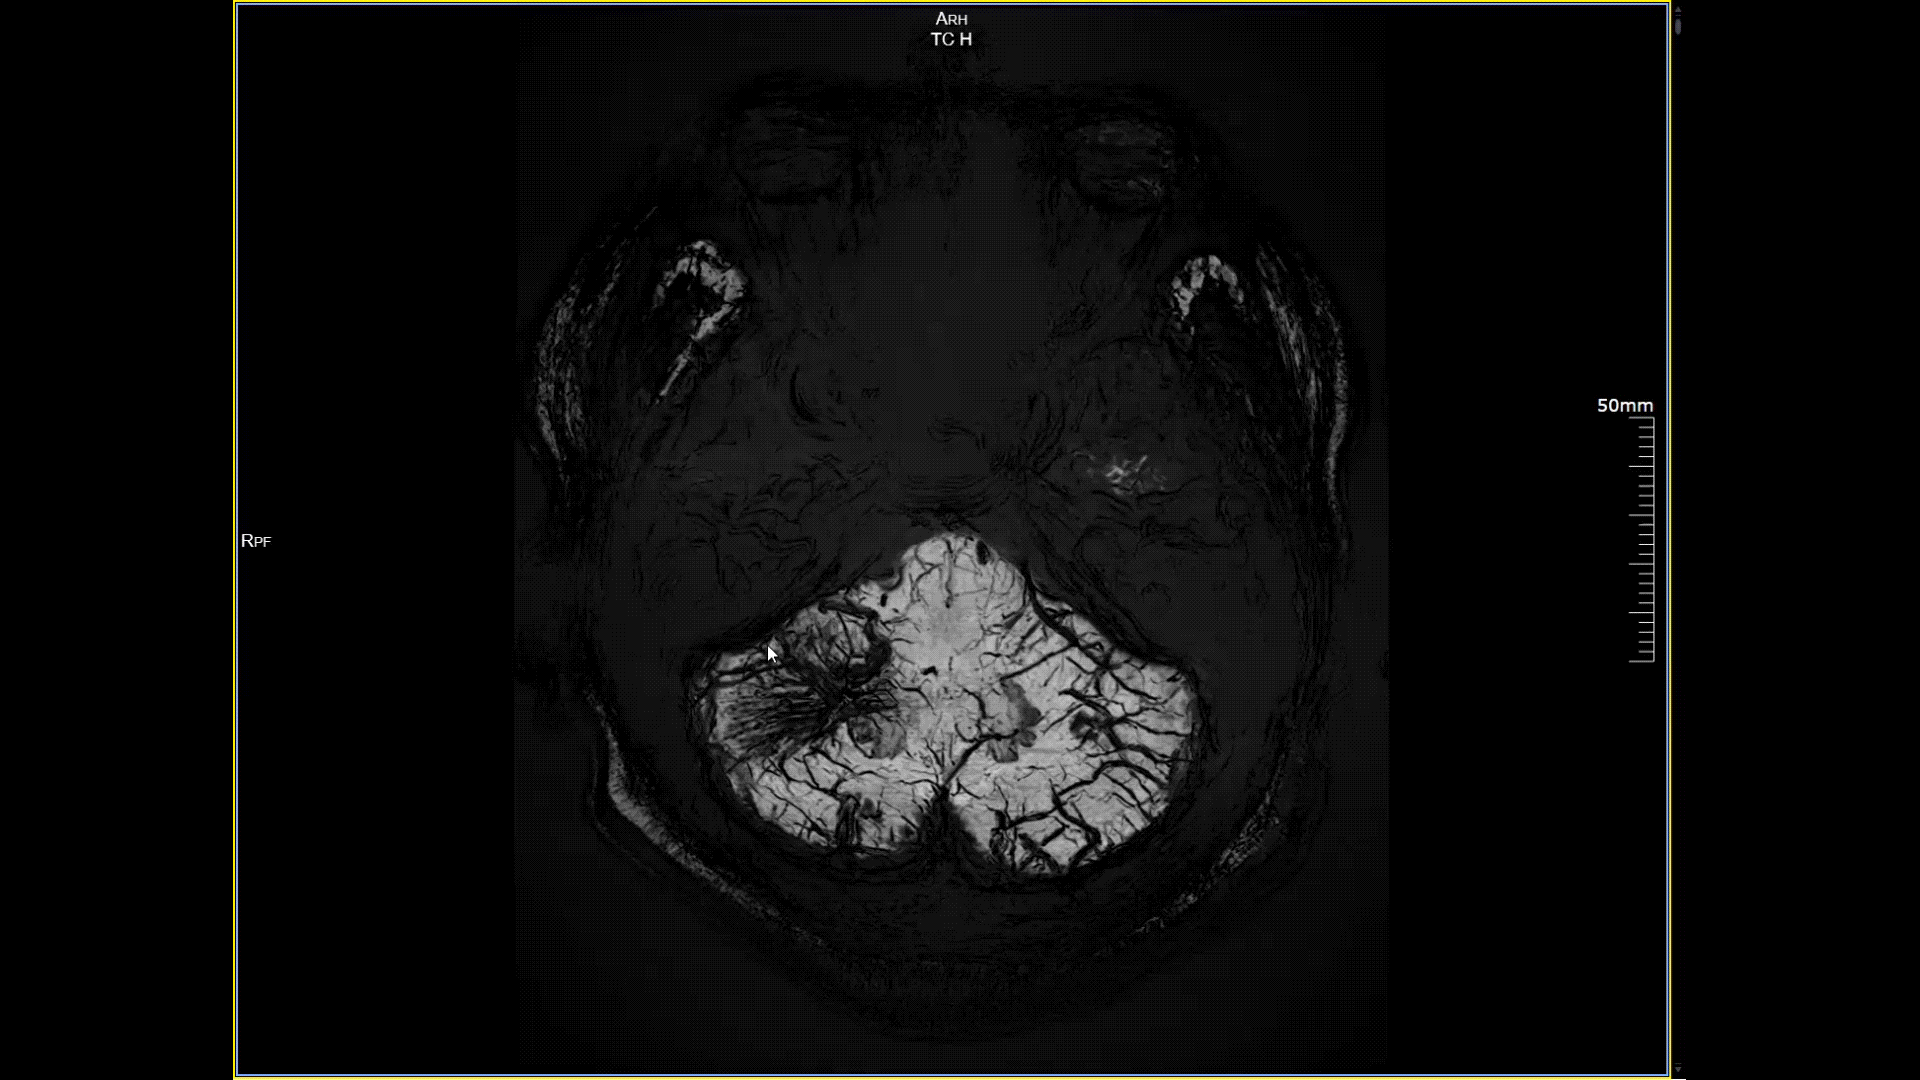

磁敏感成像SWI,分辨率0.2*0.2mm